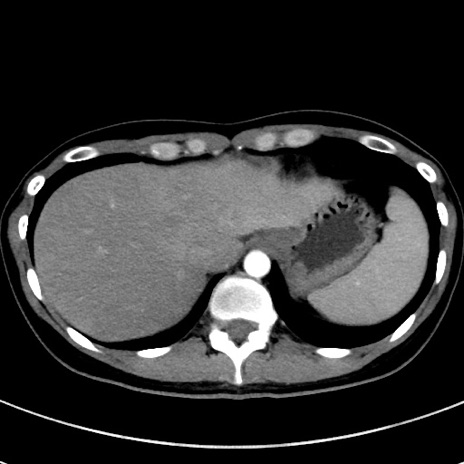

症例17(横断像)

【症例】20歳代女性

【主訴】嘔吐、下腹部痛

【現病歴】昨日夕食後に嘔吐し下腹部痛が出現。本日になっても嘔吐持続し改善しないため来院。

【身体所見】意識清明、BT 37.2℃、BP 108/67mmHg、腹部:平坦、やや硬、下腹部正中から右にかけて圧痛あり、反跳痛軽度あり、tapping pain(+)。

【データ】WBC 13600、CRP 14.94